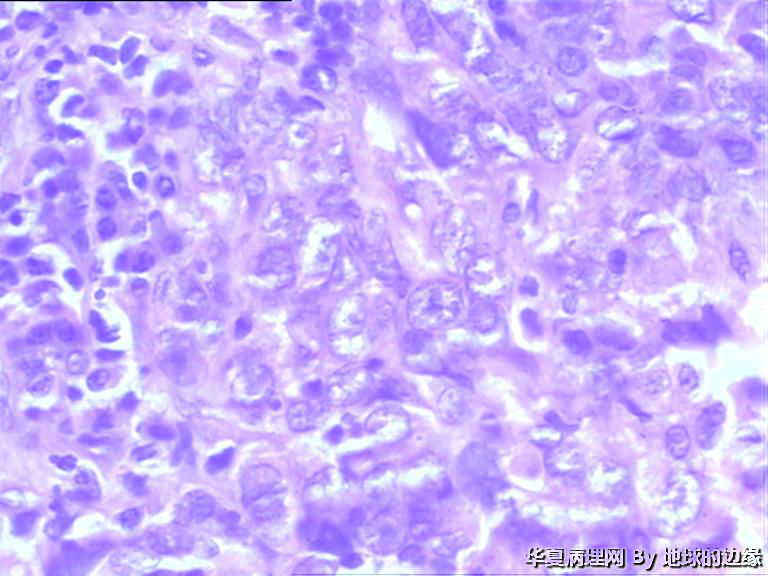

病人女性,48岁

MRI示:右肱骨肿瘤待排,包块大小为10x8cm,活动度差,边界欠清,鱼肉组织(白色),肿块侵犯至骨外    组  织。

• 右肱骨肿瘤待查图3

图3

恶性。是转移还是原发,是骨肉瘤还是浆母?需要进一步资料并标记。

考虑肉瘤,转移癌也排除一下吧

目前Vimentin阳性,P53阳性,AFP,EMA,CK7,CK20,E-ca,CR,PLAP,CD99,ER,PR,CEA,均阴性,只是没做淋巴瘤这一套了